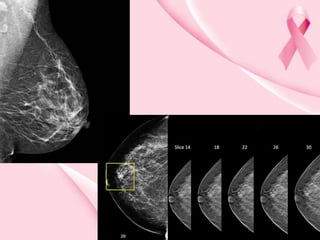

Mamografía digital

• Registra imágenes de rayos X en código de

computadora y no en película de radiografía.

Ventajas:

• Almacenamiento electrónico, facilita

su fácil acceso.

• Facilita diferenciación sutil de tejidos.

• Reduce el número de procedimientos

de urgencia o seguimiento.